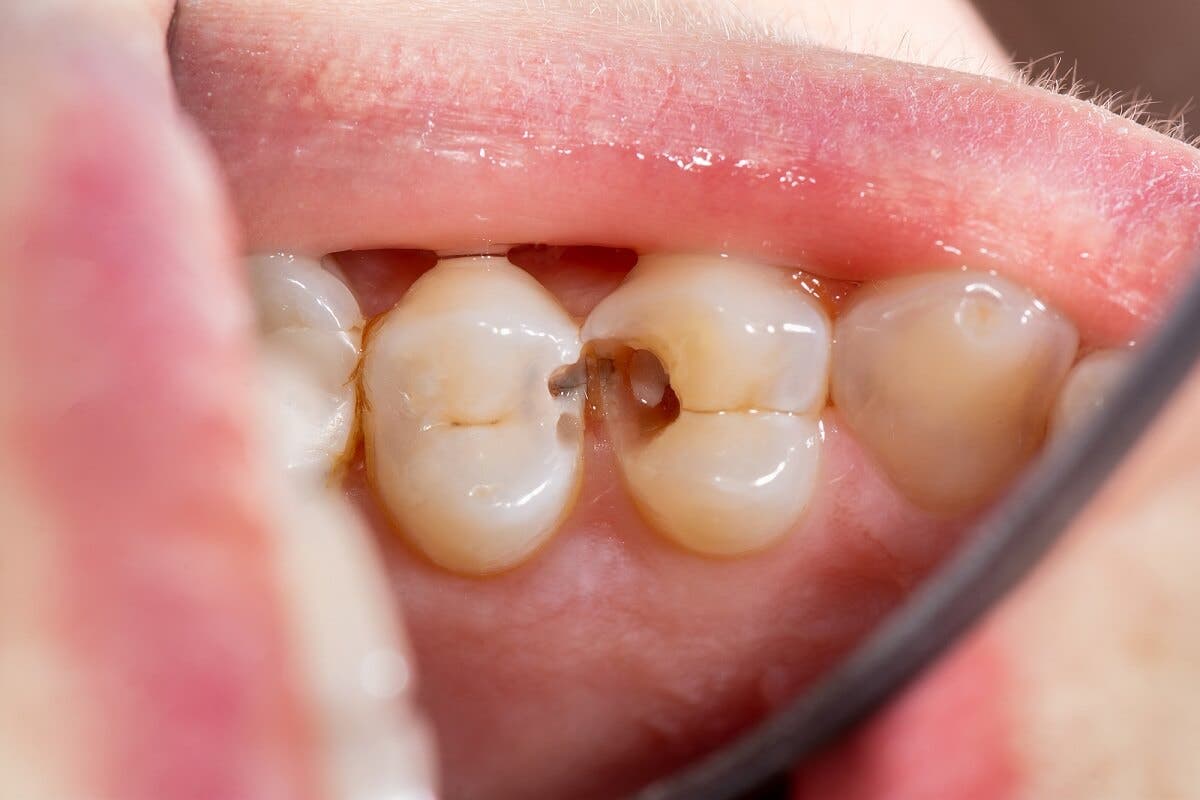

- Hull i tennene.

For eksempel er de mest akutte og intense smertene forbundet med karies. På en annen side, når små blødninger dukker opp rundt den berørte tannen, er de vanligvis et resultat av nylig oral kirurgi.